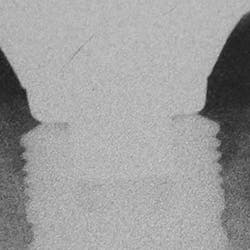

Implant manufacturing involves a high degree of precision. Implant fixture dimension, bone drill protocols, taps, and insertion devices should intimately correspond. Prosthetic components, abutment connections, and screws are also closely mated in design and production, so there is minimal tolerance between machined components. Interestingly, I hear much conversation regarding the poor fit of lower-tiered implant components, which can result in implant failure or screw loosening. Implant systems consist of CAD/CAM parts, with components that are fabricated with a high degree of homogeneity. Vertical and anti-rotational discrepancies exist and vary between companies and the types of connection used,12 but studies indicate that the fit of mismatched components improves with the application of mechanical torque to a clinically acceptable level.13 Clinicians also need to understand that there is more to screw loosening than the system-such as passive fit of the casting, proper torque values and preload,14 adequate interproximal contact, and the most often overlooked and misunderstood aspect of dentistry . . . occlusion (figures 7-9).

Figure 7

Figure 8

Figure 9

Figures 7-9: Implant site No. 19 has been restored for one year without any incident of screw loosening. Bone levels are excellent (figure 7), but a small gap is evident between the abutment and fixture platform upon radiographic evaluation (figure 8), due to the usage of implants from two "compatible" manufacturers. The tissue levels are excellent, despite a "mismatch" in components. Notice the gingival recession and the lack of attached tissue15,16 on distal implant site No. 18 (figure 9). However, with critical examination of implant No. 18, it is possible that the transmucosal element is too long and the overlying gingival tissues too thin, making this particular fixture inappropriate for this site. (Perhaps a bone-level fixture would have been a better choice.)